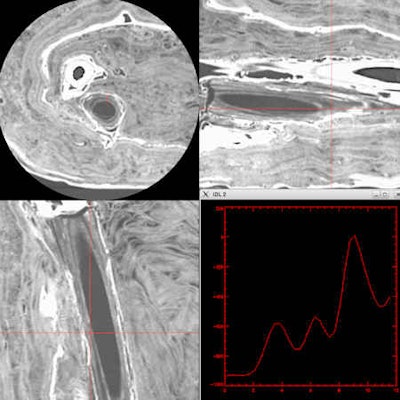

Using a 320-slice CT scanner (Aquilion One, Toshiba Medical Systems Europe), van Beek and colleagues performed 0.25 mm volumetric imaging using two kV settings and using maximal mAs. Additional imaging of the head was performed, using a gantry tilt to allow for better reconstruction of the head and facial bones.

Many hours of analysis followed. The radiology team spent a lot of time analyzing the images, working with forensic pathologist Dr. Elena Kranioti, lecturer in forensic anthropology at the University of Edinburgh and her anthropology team to perform measurements, study for potential cause of death or trauma, reconstruct the face, and clarify detailed information on findings discovered within the shroud.

Martin Connell, a clinical scientist at the Clinical Imaging Research Centre, did the initial 3D reconstruction using Voxar 3D visualization software. Dr. Saeed Mirsadraee, a senior clinical lecturer in radiology at the University of Edinburgh, did subsequent image postprocessing.

Two separate videos were made one of detailed 3D reconstructions and the other of a high definition volume rendering fly-through of the whole body scan (HDVR Connect software, Fovia) . "We wanted the rapid 3D interaction of Fovia's software to give the fly-through appearances, whereas we used Voxar software more for the actual measurements and to highlight some of the key findings of the mummy," van Beek said.

Most exciting was the discovery that a scroll, presumably a funerary text made of papyrus containing the mummy's lineage or name, directions for mummification, and guidance for the afterlife, had been placed in her right hand resting on a thigh."We were able to reconstruct the dimensions and the position of the scroll, and we are having discussions as to whether micro-CT may be able to make this legible," van Beek said. A team of specialists from Toshiba Medical Visualization Systems Europe performed the scroll reconstruction.